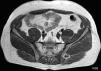

La resonancia magnética (RM) de pelvis (fig. 2) mostró edema óseo subcondral en ambas vertientes de la articulación sacroilíaca izquierda, así como discreta hiperintensidad de señal en la interlínea articular. Se identificó además miositis en la vecindad, en los rotadores izquierdos, así como en el glúteo mayor, donde el área de miositis era mayor y se acompañaba de un pequeño absceso central. Se inició, por tanto, tratamiento antibiótico con ceftriaxona y cloxacilina de forma empírica.

La ecocardiografía no mostró datos de endocarditis. Al mes se realizó una RM de control (fig. 3), que mostró persistencia del edema óseo subcondral en ambas vertientes articulares de la sacroilíaca izquierda, indicativa de persistencia de sacroilitis; en cambio, mostró desaparición del área de miositis y del absceso del glúteo mayor izquierdo, hallazgo esperable debido al corto plazo desde la primera RM. La evolución del paciente fue favorable tanto clínica como analíticamente con el tratamiento antibiótico mantenido durante 6 semanas.